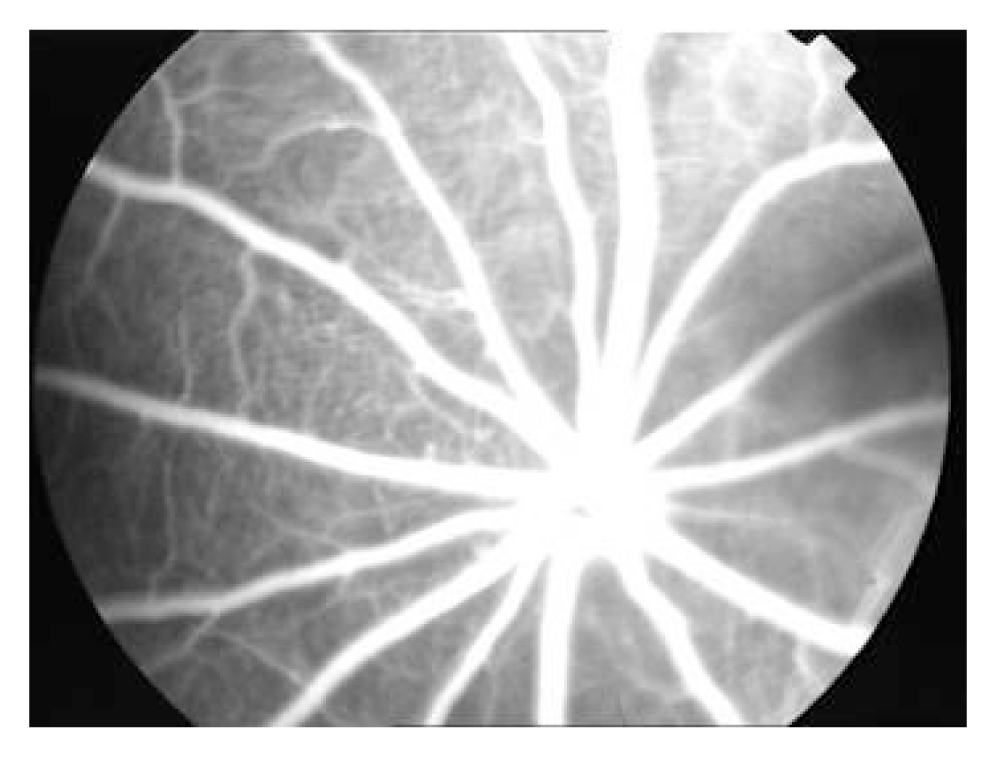

Figure 3.

No fluorescein leakage was observed under FFA in normal BN rats